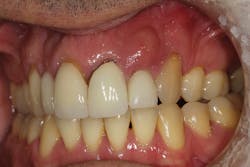

Type 1 socket—Buccal plate present and soft tissue present

• Type 1 socket (figure 19)—Thick biotype, posterior tooth, and buccal plate present: no graft needed